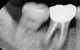

MTA 신경치료

MTA신경치료를 통한 치조골 재생

MTA신경치료